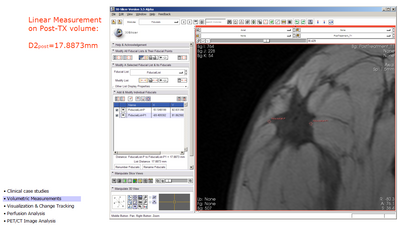

Linear Measurement (from draft slides)

measuring pre-TX tumor with fiducials, orthogonal dimension

• Linear Measurements:

• scroll to slice with largest diameter Dmax

• measure Dmax and orthogonal Dmax on both treatment timepoints using the linear measurement widget.